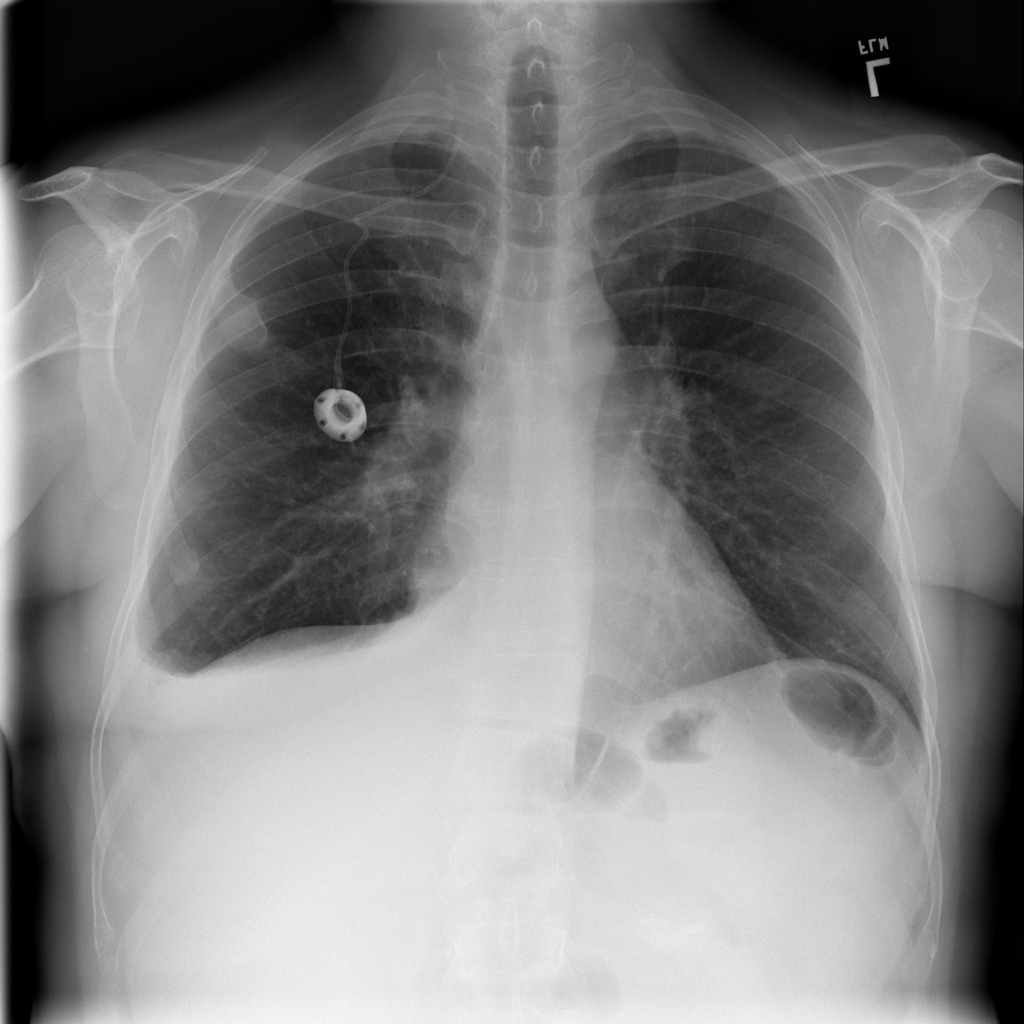

Pleural Effusion

Pleural effusion means extra fluid has collected around the lung in the pleural space. It can happen with heart problems, infection, inflammation, or other underlying conditions.

Showing up to 90 reference images for Effusion.

PAT-86C8 · IMG-000Effusion

PAT-86C8 · IMG-000

PA